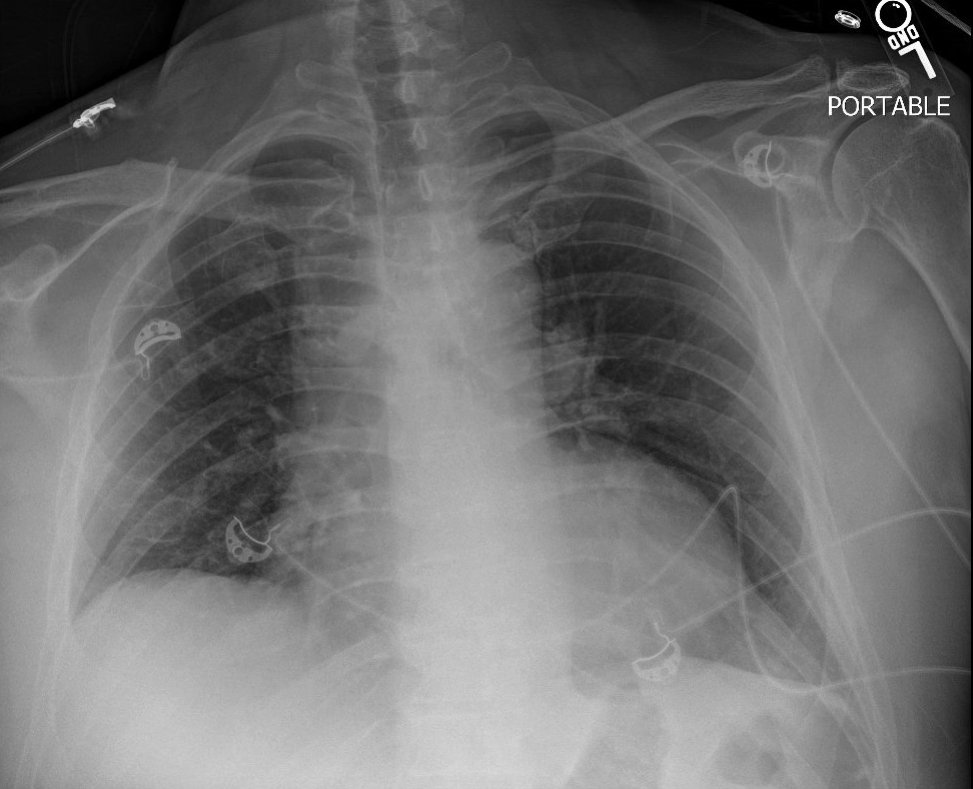

Our patient has clear lungs on exam and on chest x-ray.

This narrows our differential even further. Hypoxemia with elevated A-a gradient and clear lungs would be incompatible with most causes of physiologic shunt and impaired diffusion.